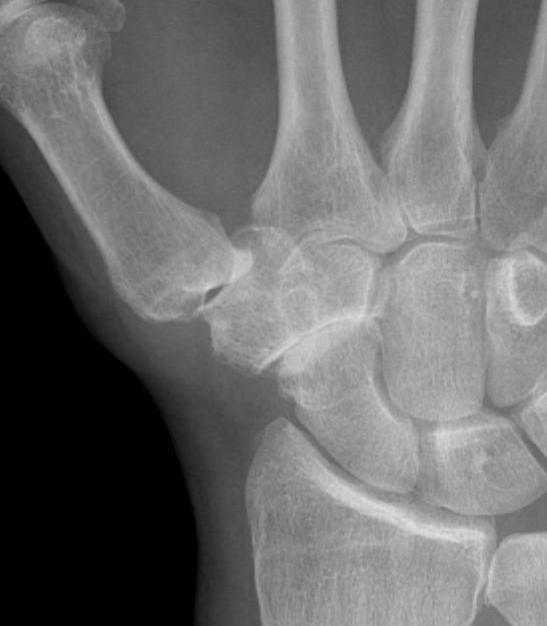

Isolated STT osteoarthritis

OA of the scapho-trapezium-trapezoidal (STT) joints

Third most common wrist osteoarthritis after CMC OA and SLAC wrist